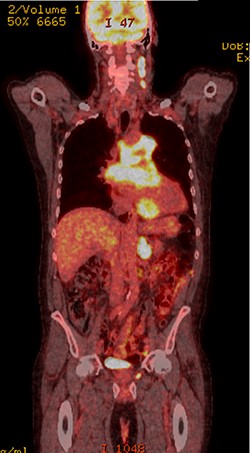

Further staging imaging was recommended by the radiology team. A CT head scan demonstrated no abnormalities, whereas CT chest–abdomen–pelvis (CAP) found significantly enlarged necrotic mediastinal lymph nodes with invasion into the pericardium and heart; bilateral adrenal nodules (suspicious for metastases) and appearances consistent with a lymphoproliferative disorder. The testicular biopsy found large lymphocytes with abundant cytoplasm and prominent nucleoli consistent with a diffuse large B-cell lymphoma (DLBCL). A positron emission tomography (PET) scan was organized at the request of the oncology team (Figs 4 and 5).

PET scan (transverse plane) demonstrating an enhancing lesion encroaching the heart with necrotic lymph nodes.

PET scan (coronal plane) showing intensely metabolically active lymphadenopathy on both sides with extra-nodal involvement through lymphoid tissue, adrenals and muscle.

He was subsequently diagnosed with stage IV (Lugano) DLBCL and underwent the R-CHOP chemotherapy regimen. He has responded well to his oncological treatment.